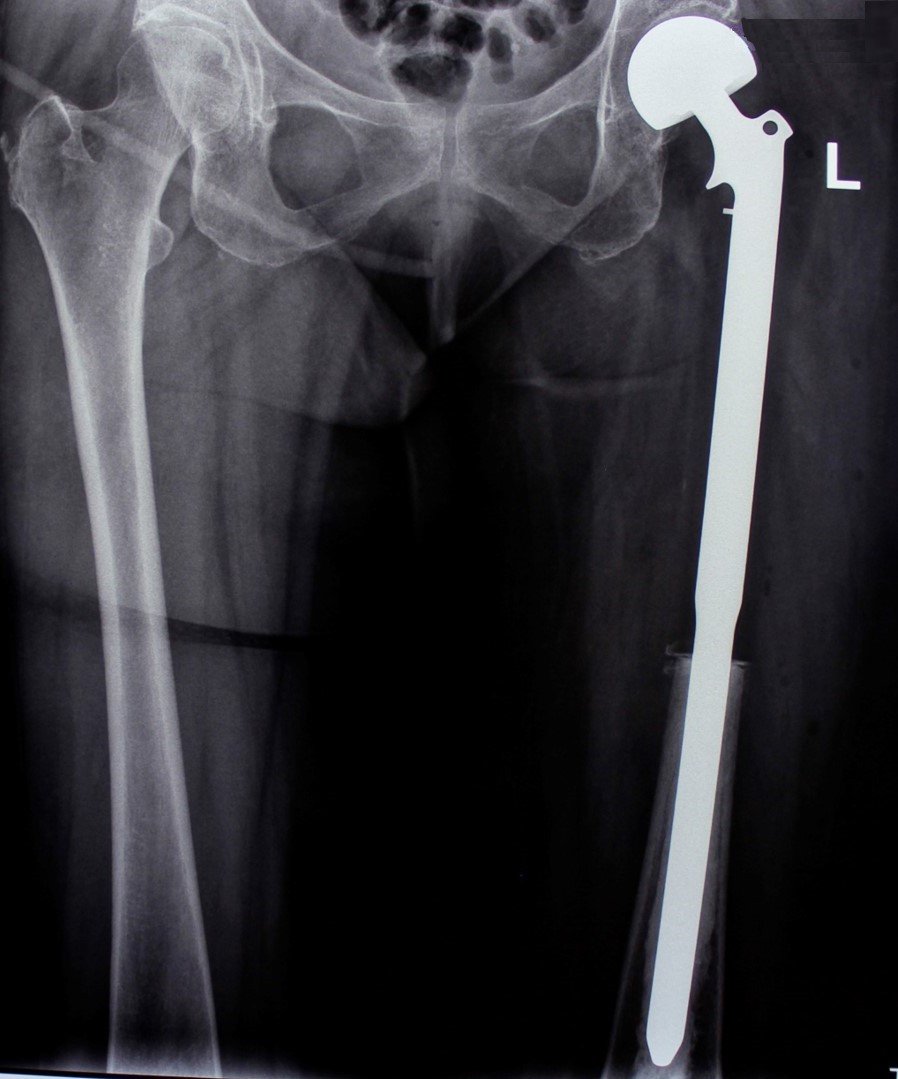

2. Остеосаркома большеберцовой кости

17-летний юноша обратился в МЦ ''Наири'' с жалобами на боли в области коленного сустава. После прохождения обследования у пациента была диагностирована остеосаркома большеберцовой кости.

После получения предоперационной химиотерапии в МЦ ''Наири" была проведена органосохраняющая операции – сегментарная резекция верхней трети большеберцовой кости и коленного сустава, замещение образовавшегося костно-суставного дефекта индивидуальным, изготовленным на заказ эндопротезом. В послеоперационном периоде пациент продолжил показанную по протоколам химиотерапию. В настоящее время лечение завершено, признаков прогрессирования заболевания нет, оперированная конечность функционально пригодная, опороспособность полная.

До операции

После операции